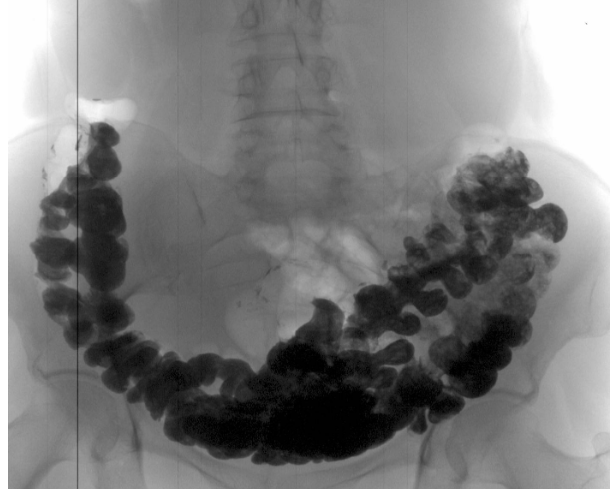

Подивіться знімки органів людей, у яких усе почалося з неприємного запаху з рота, закрепів та печії, а закінчилося доповіддю патологоанатома.

‘’Рак товстої кишки у жінки зі скаргою на часті закрепи’’